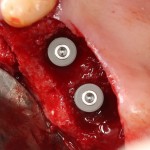

Для примера мы возьмём немедленную имплантацию:

Никогда, почти никогда нам не удаётся сохранить конфигурацию лунки удалённого зуба в первоначальном виде — вслед за удалением неизбежно следует атрофия краевой кости, которую мы деликатно называем «перестройкой» или «ремоделированием». Это совершенно нормальный физиологический процесс, о нём я подробно написал здесь>>, рекомендую почитать.

Так вот, из-за этой атрофии вокруг платформы имплантата остаётся фиброзный ободок, видимый на снимке:

В таком состоянии он остаётся много лет, не вызывая какого-либо беспокойства у пациента. Однако, для некоторых докторов он является поводом начать разговор о несостоятельности имплантата — «патамушта ета периимплантит». Хотя, я повторюсь, какая-либо воспалительная симптоматика и здесь отсутствует, в принципе.

Иными словами, далеко не каждый случай убыли костной ткани вокруг имплантата (или имплантатов) можно считать периимплантитом. Главным его признаком является выраженная воспалительная симптоматика. Если таковая отсутствует, то мы называем это атрофией (если хотите, «физиологической атрофией»), тактика работы с которой будет принципиальным образом отличаться.